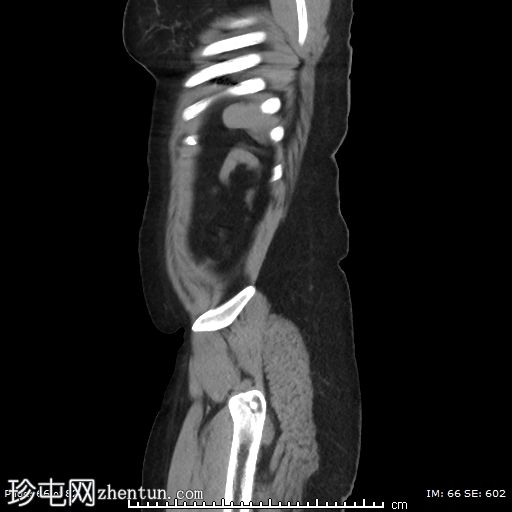

轴位增强扫描(门静脉期)

左侧附件区可见一巨大囊性病变,大小约9 x 12 cm,主要呈液体密度,囊壁光滑薄。

邻近一复杂囊性成分,向中线延伸,大小约10 x 9 cm,内部可见分隔及不均匀液体密度,提示内容物可能为出血性或部分复杂性。

左侧附件区可见一边界清晰的卵圆形低密度肿块,大小约4 x 4 cm,囊壁厚,内部为软组织、脂肪和液体混合密度,符合成熟囊性畸胎瘤(皮样囊肿)的影像学表现。

左侧附件血管蒂扭转,形成血管和软组织呈漩涡状排列,高度提示卵巢扭转。

可见轻度卵巢周围脂肪条索状改变和少量邻近盆腔积液,可能为继发性充血和水肿。

由于左侧附件增大的组织结构压迫,子宫向右侧移位。

右侧附件未见异常。

阑尾大小和直径正常,无急性阑尾炎的证据。